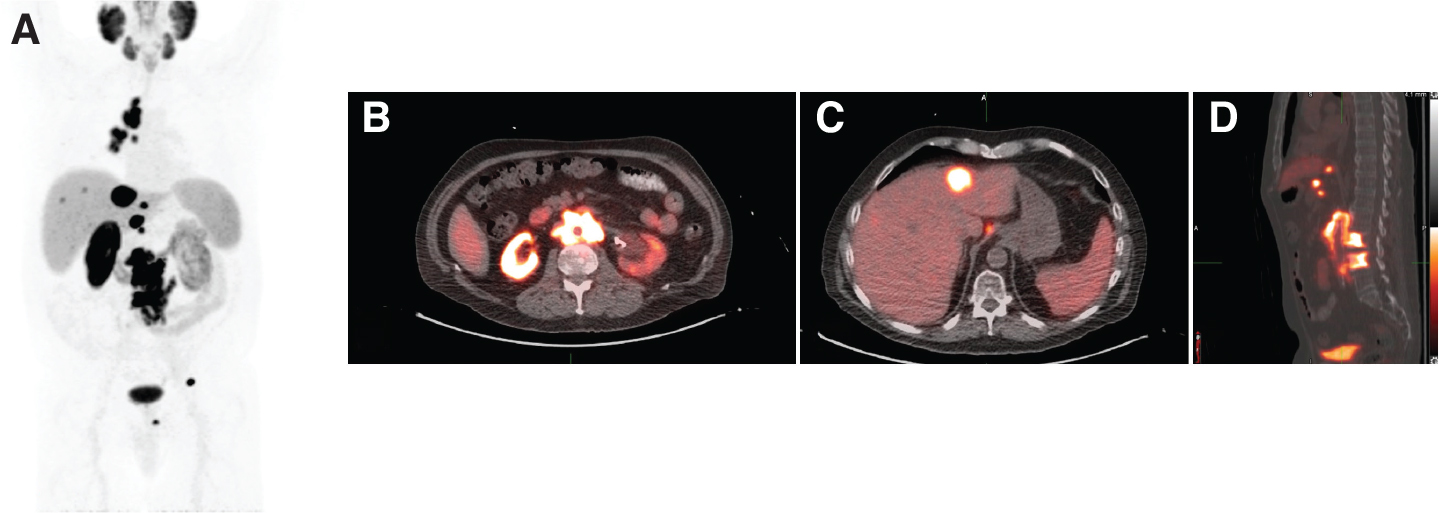

Fig 1

Figure 1. An 89-year-old male with mCRPC eligible for 177Lu-PSMA-617. A, Maximum intensity projection (MIP) image from a PSMA PET scan showing intensely PSMA-avid mediastinal and retroperitoneal lymphadenopathy, as well as intensely PSMA-avid metastatic lesions in the liver and lumbar spine. B, Fused axial image more clearly demonstrating extensive PSMA-avid retroperitoneal lymphadenopathy. C, Fused axial image more clearly demonstrating intensely PSMA-avid liver metastases. D, Fused sagittal image showing PSMA-avid osseous metastases in the lumbar spine.